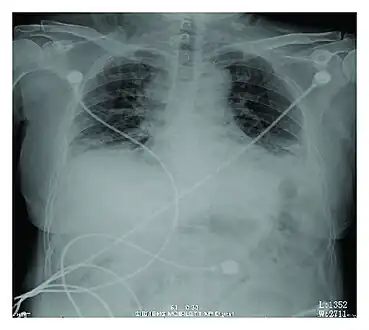

Rapid progression from initial symptoms to respiratory failure is a key feature. An X-ray that shows ARDS is necessary for diagnosis (fluid in the small air sacs (alveoli) in both lungs). In addition, a biopsy of the lung that shows organizing diffuse alveolar damage is required for diagnosis. This type of alveolar damage can be attributed to nonconcentrated and nonlocalized alveoli damage, marked alveolar septal edema with inflammatory cell infiltration, fibroblast proliferation, occasional hyaline membranes, and thickening of the alveolar walls. The septa are lined with atypical, hyperplastic type II pneumocytes, thus leading to the collapse of airspaces. Other diagnostic tests are useful in excluding other similar conditions, but history, X-ray, and biopsy are essential. These other tests may include basic blood work, blood cultures, and bronchoalveolar lavage. The clinical picture is similar to ARDS, but AIP differs from ARDS in that the cause for AIP is not known.